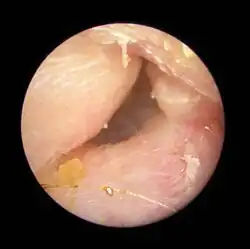

| Exostoses in the ear canal, as seen through otoscopy | |

Surfer's ear is the common name for an exostosis or abnormal bone growth within the ear canal. They are otherwise benign hyperplasias (growths) of the tympanic bone thought to be caused by frequent cold-water exposure.[1] Cases are often asymptomatic.[1] Surfer's ear is not the same as swimmer's ear, although infection can result as a side effect.

Irritation from cold wind and water exposure causes the bone surrounding the ear canal to develop lumps of new bony growth which constrict the ear canal. Where the ear canal is actually blocked by this condition, water and wax can become trapped and give rise to infection. The condition is so named due to its high prevalence among cold water surfers, although it can occur in any water temperature due to the evaporative cooling caused by wind and the presence of water in the ear canal.

The normal ear canal is approximately 7 mm in diameter and has a volume of approximately 0.8 ml (approximately one-sixth of a teaspoon).[5] As the condition progresses, the diameter narrows and can even close completely if untreated, although people generally seek help once the passage has constricted to 0.5–2 mm due to the noticeable hearing impairment. While not necessarily harmful in and of itself, constriction of the ear canal from these growths can trap debris, leading to painful and difficult to treat infections.